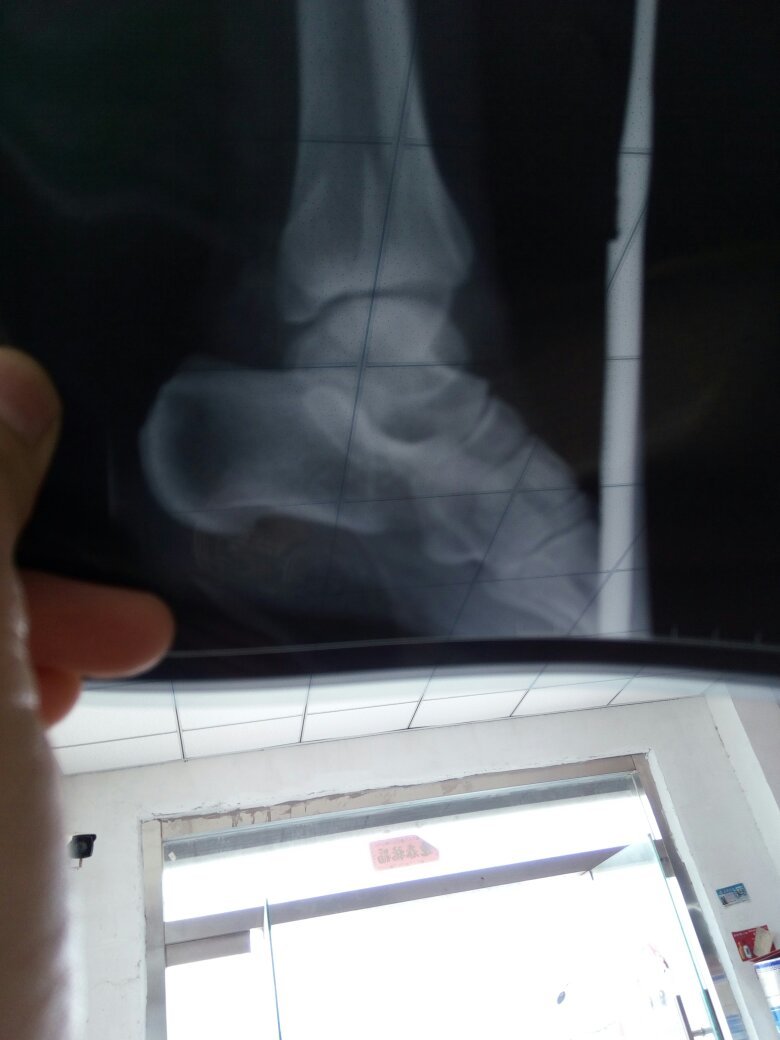

怀孕七个月了,左脚踝两边骨折,到生孩子时候能慢慢走路吗?后面有片子帮我看看吧 谢谢 点击展开 133*****340_heC3 2016-09-23 10:10 满意回答 您好,根据描述,考虑可以寸细评石膏外固定。怀孕期间,尽量不做。拍径劣片概豆放射检查 cn#afBBaVapka 2016-09-23 10:14 宝宝知道提示您:回答为网友贡献,仅供参考。 相关问题 那要是脚踝怀疑骨折,是拍什么片子呢 你好,我在排卵期陪我儿子拍脚踝骨折片子,现在怀孕42天了 脚趾骨折57天了,脚踝还是肿,现在可以下地走路了吗?同房影响恢复吗?拿热水泡脚有好处吗?谢谢